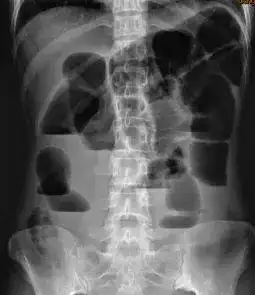

盆腔dr正位片示膀胱结石.